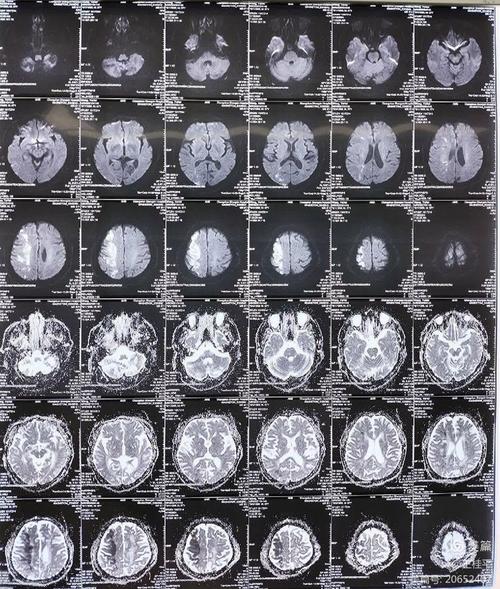

“稍微有点脑梗”在医学上通常指什么?

医生在口头沟通时,为了方便患者理解,可能会用“稍微有点”这样的词,在影像学上,这很可能对应以下几种情况:

- 腔隙性脑梗塞: 这是最常见的情况,它不是我们通常想象的那种大面积、致命性的脑梗,它是因为大脑深处一些非常细小的血管堵塞了,导致一小块脑组织缺血、坏死,这个“小块”非常小,可能只有几毫米,通常不会引起明显的、严重的症状(比如瘫痪、失语等),很多人甚至根本不知道自己有过。

- 脑白质变性/缺血脱髓鞘: 这是一种与年龄、高血压、高血脂、糖尿病等相关的慢性改变,可以想象成大脑的“电线绝缘层”有点老化了,这本身不是脑梗,但它反映了长期的小血管功能不太好,是未来发生脑梗的一个风险信号。

- 无症状性脑梗塞: 梗塞的病灶确实存在,但因为位置不关键或范围太小,没有引发任何可以察觉的临床症状。

医生说“稍微有点”,大概率是指发现了一些陈旧性的、范围很小的、没有引起明显症状的缺血病灶,这更像是一个“健康警报”,提醒您需要关注和管理自己的脑血管健康,而不是一个“疾病判决”。